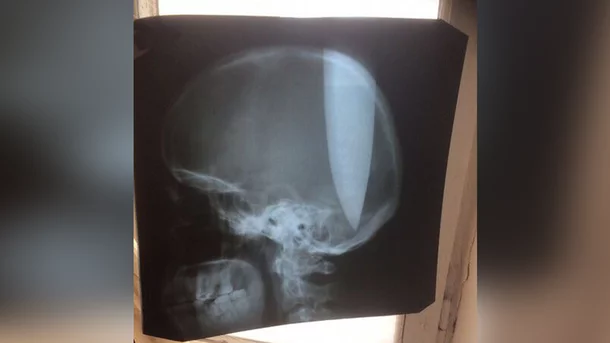

Мозг не пострадал :клас: Аккурат промеж полушарий...

Как он умудрился его так всадить? :незнаю:

Чудик насморк лечил :іржач:

А. Это тот, который в голову себе нож засунул... я в новостной ленте видел заголовок...